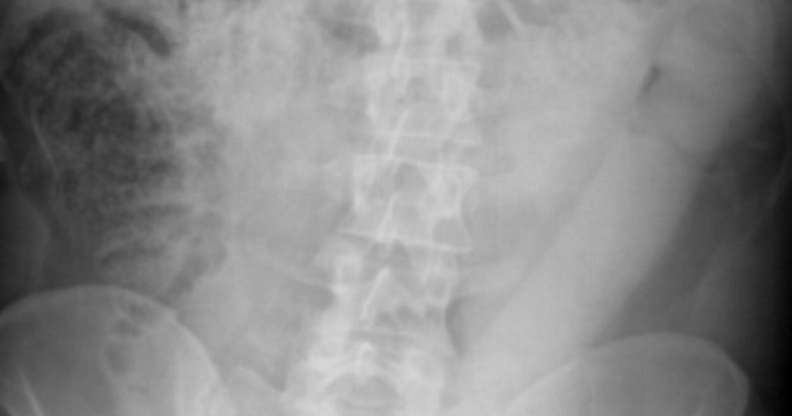

The 23-inch dildo was stuck firmly inside the man. (Wikimedia Commons)